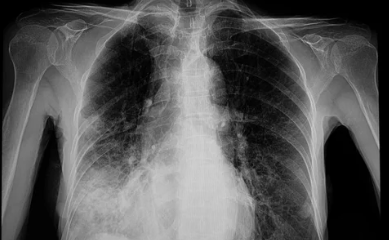

6. 증상 관리와 조기 진단의 중요성

방사선 폐렴의 초기 증상은 다른 호흡기 질환과 유사하므로, 조기에 정확한 진단을 받는 것이 중요합니다.

- 의사 상담:

기침, 흉통, 호흡 곤란 같은 증상이 나타나면 즉시 담당 의사와 상담하세요. - 정기적인 폐 기능 검사:

방사선 치료 후 일정 기간 동안 폐 기능을 모니터링하고, 변화가 감지되면 바로 치료를 시작해야 합니다. - 약물 치료:

초기 단계에서는 항염증제나 스테로이드 치료로 염증을 줄이고 증상을 완화할 수 있습니다. - 생활습관 개선:

금연, 적절한 운동, 균형 잡힌 식단을 통해 폐 건강을 유지하는 것이 중요합니다.